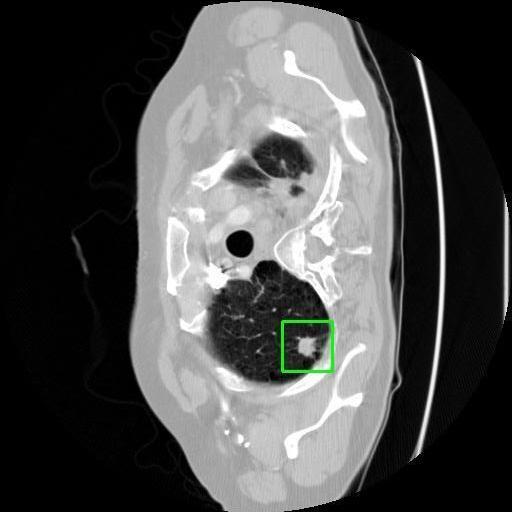

We developed an AI-based system using deep learning models for analyzing lung CT scans to detect and classify pulmonary nodules. We chose the YOLOv11 architecture for its enhanced object detection capability and adapted it specifically for medical imaging, incorporating pixel-level precision and severity classification.

Classification into three severity levels with colored bounding boxes.

Designed a severity classification system that categorizes nodules into null, moderate, and severe using colored bounding boxes, assisting in rapid clinical decision-making.